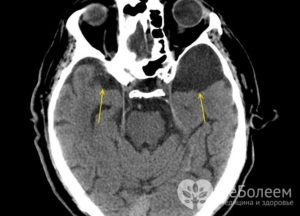

На сегодняшний день основными методами диагностики и последующего прогноза данной болезни являются МРТ (магнитно-резонансная томография) и КТ.

С ее помощью можно увидеть место расположения перивентрикулярного глиозного очага и атрофических рубцовых следов внутри головного мозга без вскрытия черепной коробки, оценить их форму, размеры и интраселлярный рост.

Кроме того, данные способы обследования позволяют сделать дифференциальную диагностику промежуточного состояния между доброкачественной кистой и злокачественной опухолью. После внутривенного введения специального контрастного вещества его продукт накапливается в опухолевых тканях, а киста при этом не становится контрастной.

- КТ и МРТ головного мозга — на данный момент самые достоверные методы обследования, позволяющие не только обнаружить кисту и определить её точную локализацию, но и узнать её гистологическую структуру. Для выявления такой патологии, как киста головного мозга, чаще используют МРТ, так как этот метод более чувствителен к мягким тканям и не даёт «слепых зон» в отличие от КТ. Имеется в виду, что при использовании КТ плохо визуализируются структуры мозга, расположенные в задней черепной ямке. Если всё-таки нет возможности провести МР исследование, то выполняют КТ с внутривенным усилением, то есть вводится контрастное вещество;